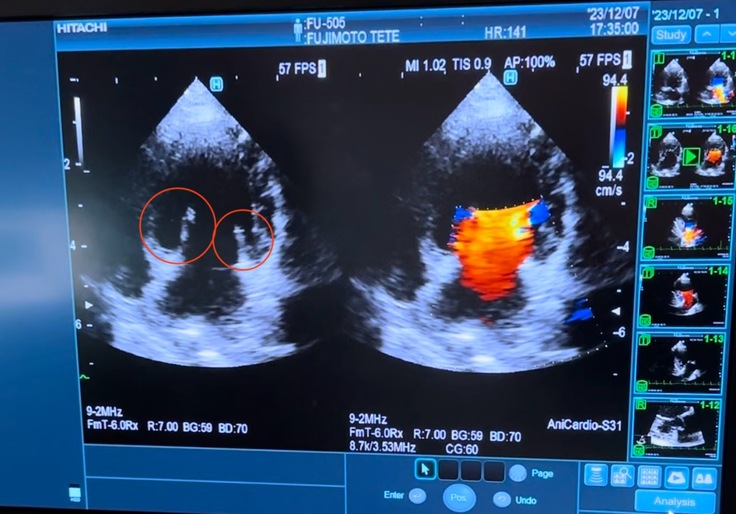

昨年12月7日の心臓検査の診断結果です。レントゲン検査では、心臓が肥大し気管を圧迫しています。

獣医師によれば、下記画像の

左側の赤丸部分は便が正常に閉じていない状態、

右側の色付き部分は便が閉じないことによる血液の逆流を示す。

ということでした。